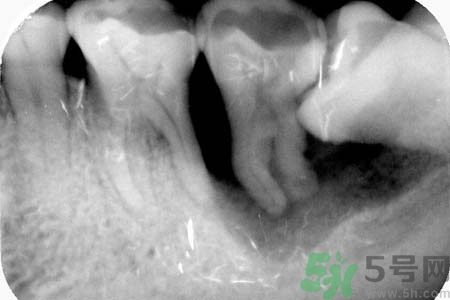

5、如果智齒經常疼,而且疼的比較厲害,可能已經引發(fā)牙冠周軟組織發(fā)炎,所以導致智齒腫脹、疼痛;再如果智齒長的位置很歪,影響其它牙齒正常咀嚼,也影響美觀,最好是考慮拔牙。拔牙前提是確保牙冠周圍沒有炎癥,才能安排拔牙,免除后顧之憂,拔智齒是拔牙里最難的一種,所以一定要到正規(guī)口腔醫(yī)院,請正規(guī)醫(yī)師進行專業(yè)拔牙。

6、如果智齒經常疼,而且疼的比較厲害,可能已經引發(fā)牙冠周軟組織發(fā)炎,所以導致智齒腫脹、疼痛;再如果智齒長的位置很歪,影響其它牙齒正常咀嚼,也影響美觀,最好是考慮拔牙。拔牙前提是確保牙冠周圍沒有炎癥,才能安排拔牙,免除后顧之憂,拔智齒是拔牙里最難的一種,所以一定要到正規(guī)口腔醫(yī)院,請正規(guī)醫(yī)師進行專業(yè)拔牙。